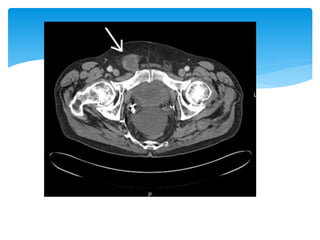

This cystogram shows the urinary bladder, part of

which has descended into a left direct inguinal hernia

(arrows).